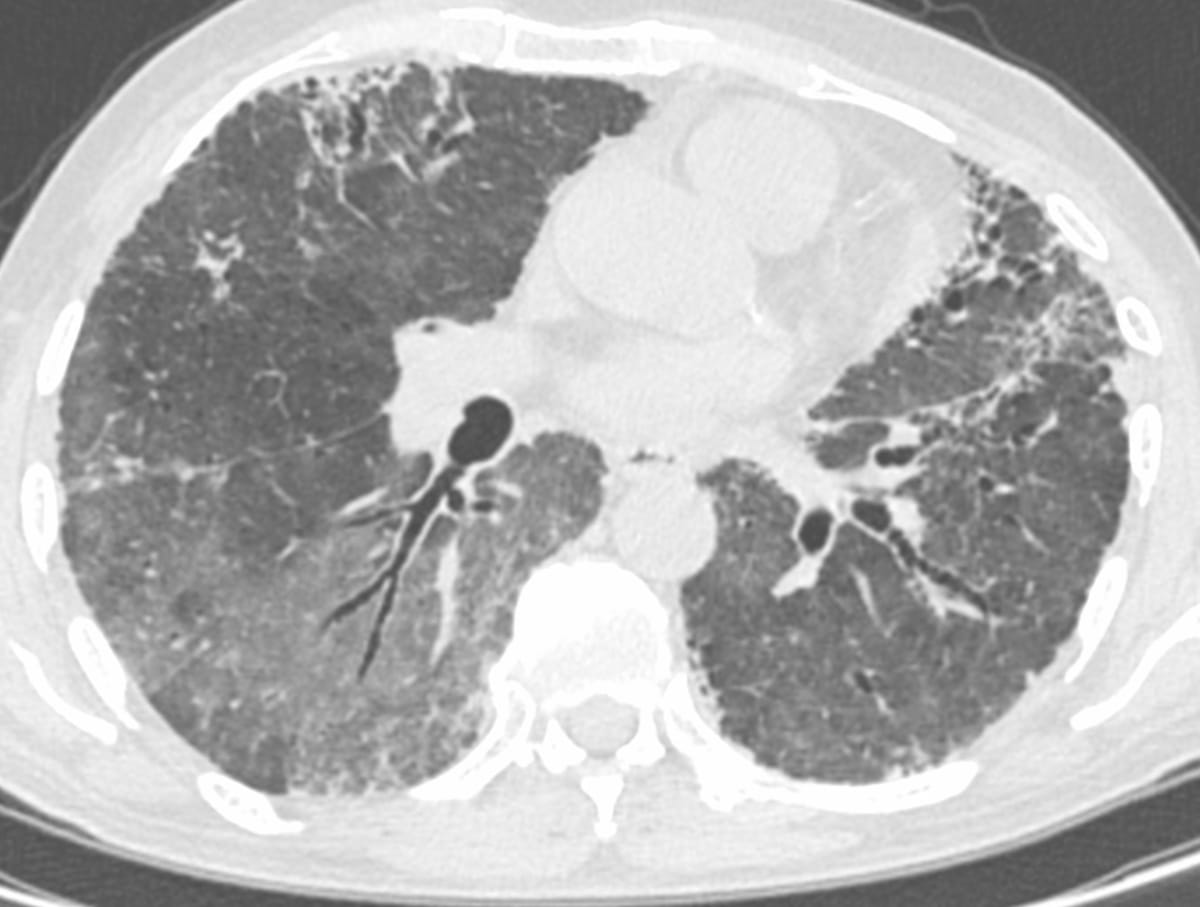

70-years old with a fibrosing ILD that shows a usual interstitial pneumonia (UIP) - like pattern on the left, but a three-density sign on the right suggesting this could be a bronchiolocentric interstitial pneumonia (BIP) pattern, suggestive of fibrotic hypersensitivity pneumonitis, if there is no underlying etiology (Fig. 1).